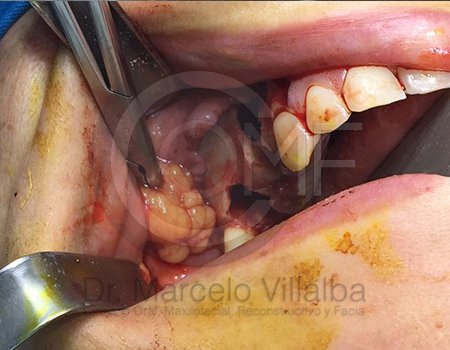

Un absceso es una acumulación de infección que puede causar dolor intenso e inflamación. Cuando el proceso infeccioso no mejora con tratamiento convencional, puede ser necesario realizar un drenaje o manejo quirúrgico.

El tratamiento depende del origen y gravedad de la infección. Puede incluir medicamentos, drenaje quirúrgico o procedimientos específicos para eliminar el foco infeccioso y evitar complicaciones.

En casos de mayor complicación deberá ser ingresado a cuidados hospitalarios, y programar el procedimiento quirúrgico que corresponda